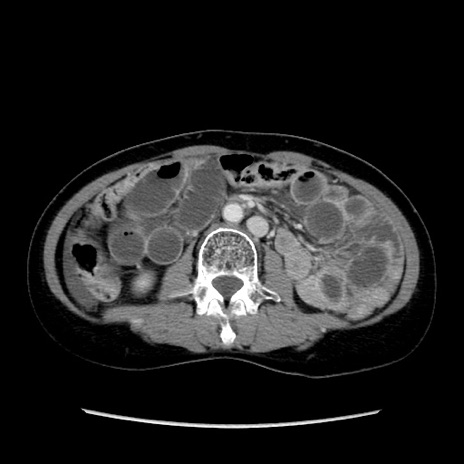

矢状断像

【症例】40歳代 女性

【主訴】上腹部痛、嘔気・嘔吐

【現病歴】約9時間前頃から急に上腹部痛、嘔気、嘔吐が出現。改善しないため救急要請。

【既往歴】子宮頚癌(広汎子宮全摘術、放射線療法)、腸閉塞

【身体所見】腹部:平坦、軟、腸雑音亢進、上腹部を中心に腹部全体に圧痛あり。

【データ】WBC 8400、CRP 0.03